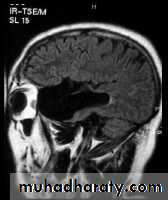

SAGITAL FLUID ATTENUATION INVERSION RECOVERY SEQUENCE: OVOID PLAQUES ( HIGH SIGNAL INTENSITY) , WHICH ARE PERPENDICULAR TO LATERAL VENTRICLE.

- the most characteristic appearance is that of peri ventricular nodular Hyper intense lesions on T2 weighted images.

-the plaques are also well seen at the gray- white matter interfaces.

-contrast enhancement after giving gadolinium occurs in the acute phase indicating activity & in the chronic phase doesn't enhance.